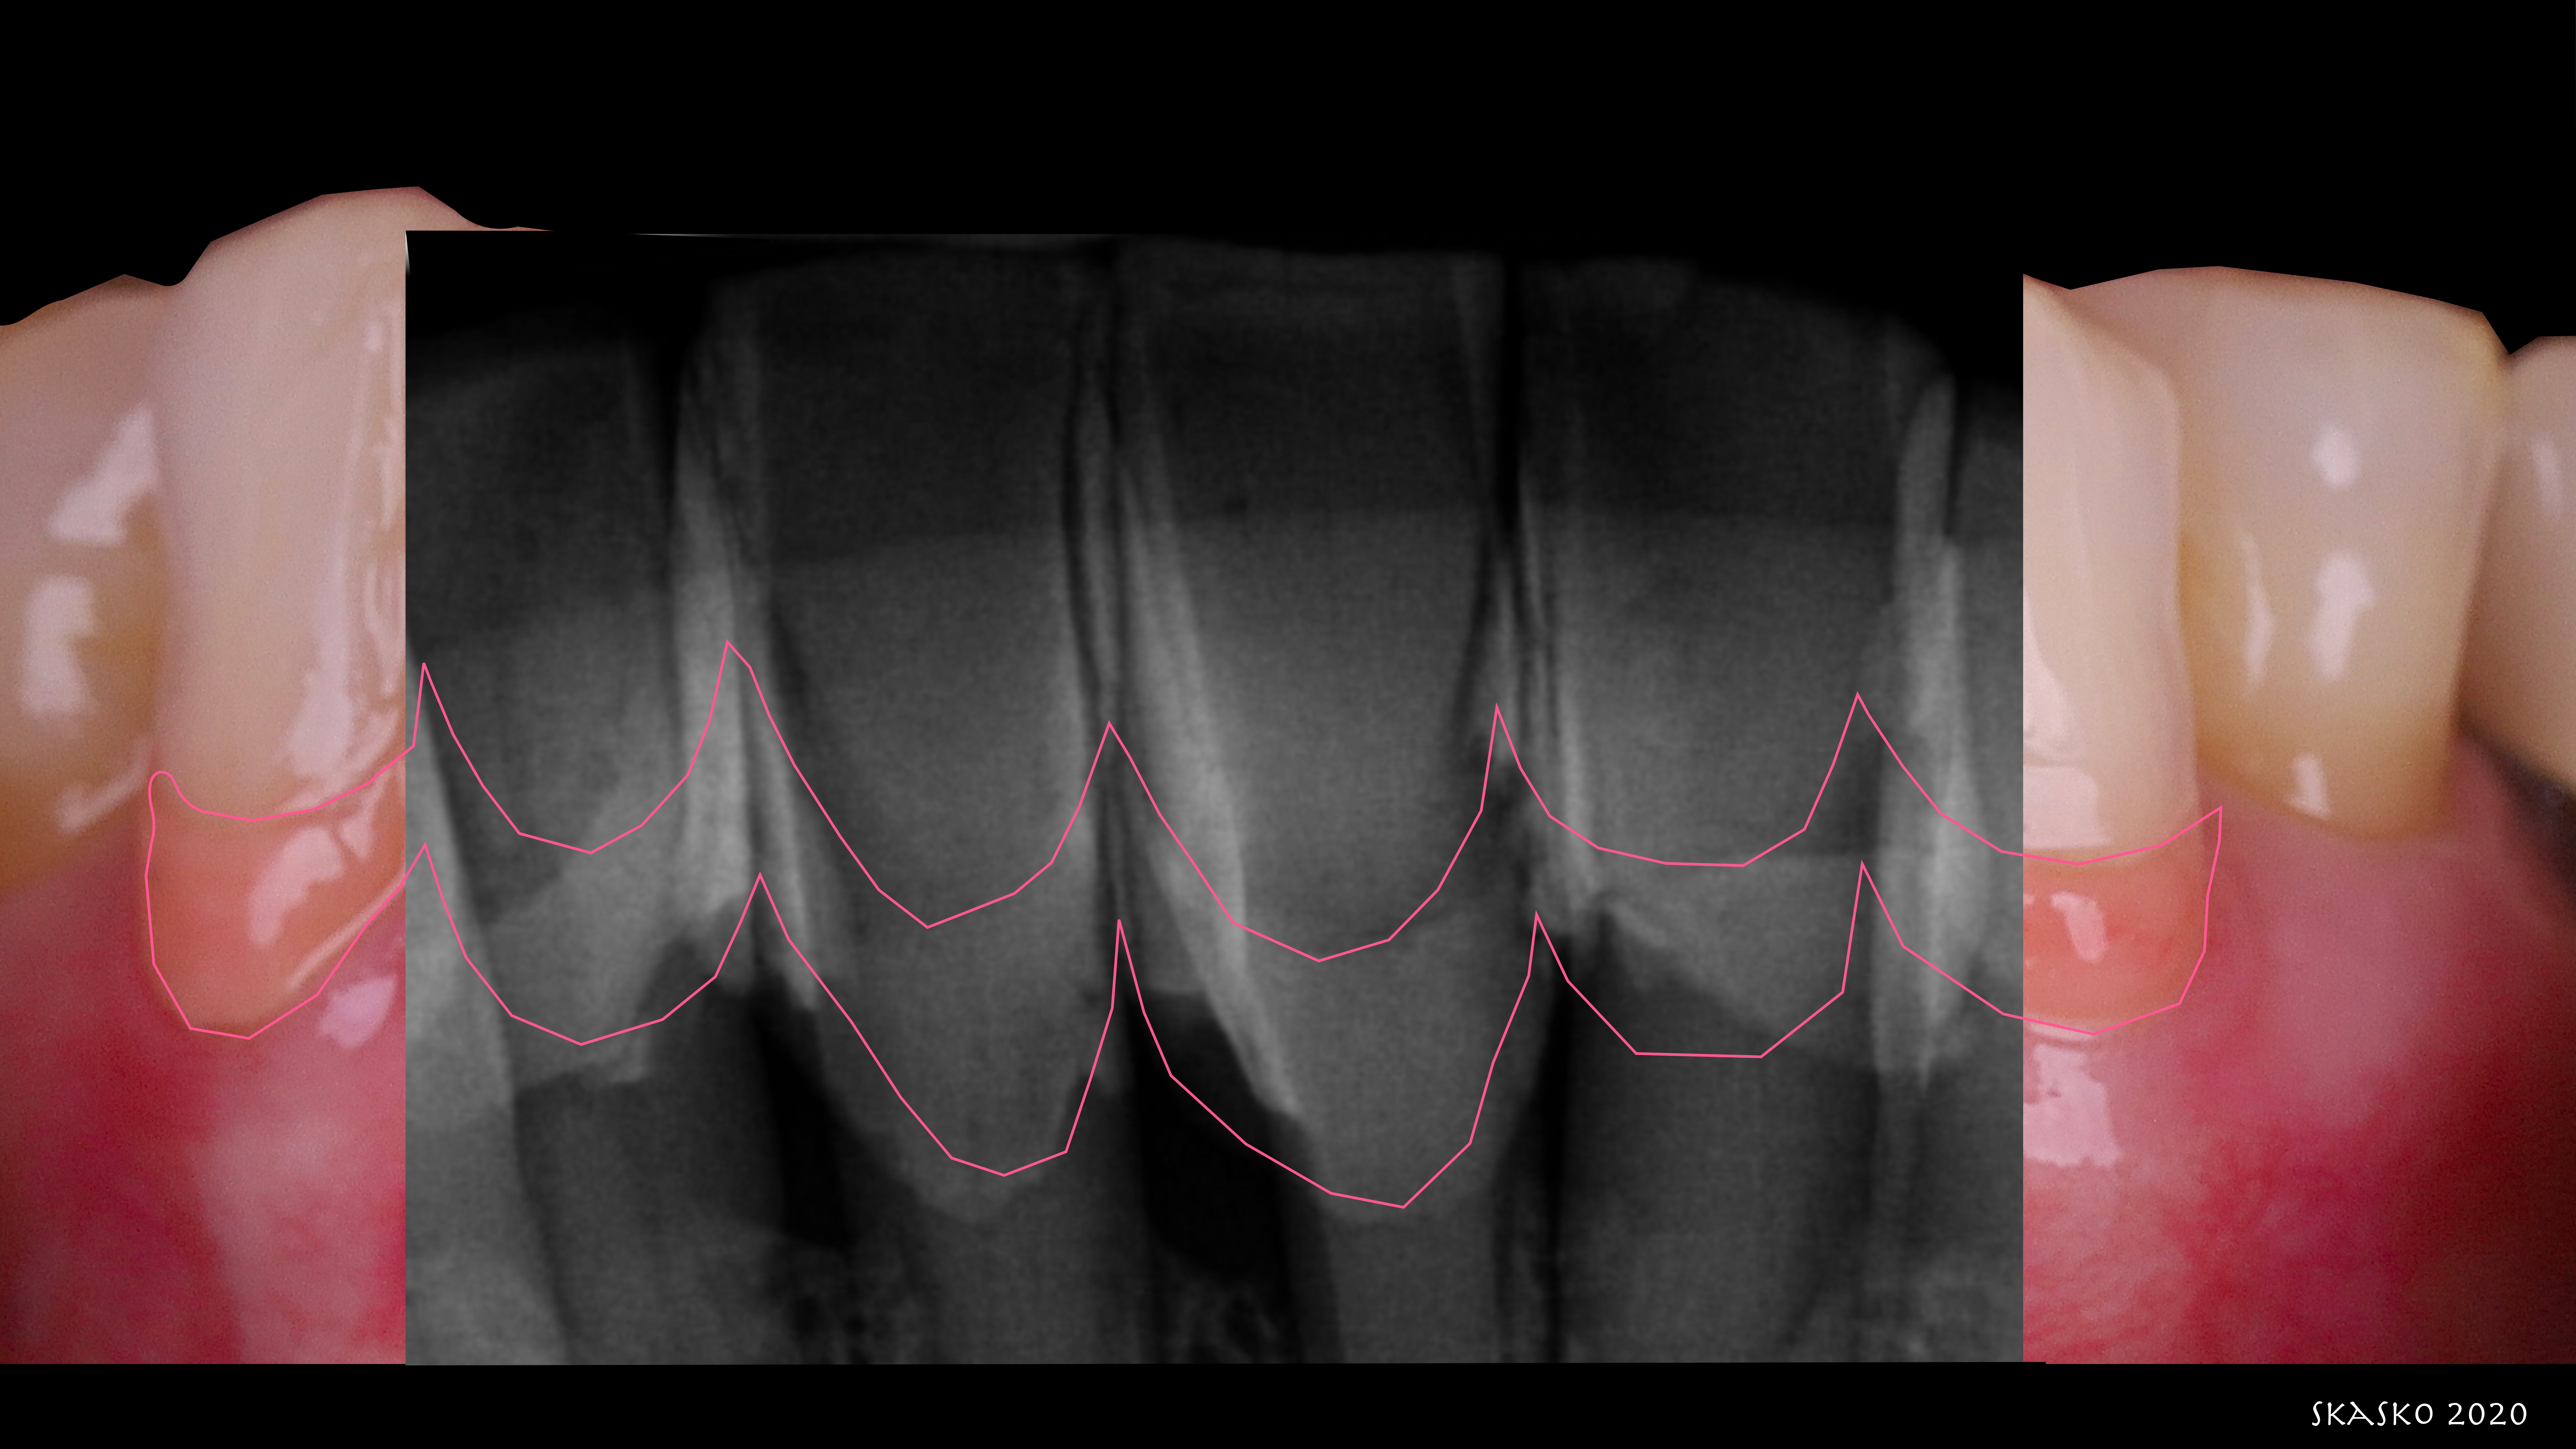

Figure 5 shows radiographs on Cody's anterior teeth that were indicated for treatment. His gingival recession and bone loss already had been classified, and he had already had orthodontics; Cody did not need orthodontics again, but it is an option in many such cases. Possible options were porcelain veneers on both the mandibular and maxillary teeth, porcelain crowns, and splinted bridges on the mandibular anterior-requiring compromising and removing a lot of tooth structure. Removal of mandibular incisors with implant placements was another option, as was a four unit bridge with or without orthodontic extrusion-knowing that as teeth are extruded, tissue and bone will be pulled with them as well.3

In the case of Cody, after doing the digital smile design, whitening was called for, and afterwards the patient was diligent with his hygiene. Before treatment, the patient presented with calculus, and so hygienist removed it before any other procedures, as teeth have to be clean at the beginning. Patient was augmented with white and pink. Figures 5 and 6, with Figure 5 showing the radiograph superimposed, show the progression. Procedures took only a few hours, and patient was so pleased he asked for additional improvements, which have included grafting and replacement of posterior crowns. Figure 6 was taken one-year post-treatment. Patient and his wife actually wrote a letter offering thanks for allowing Cody to feel proud of his smile for the first time in his life.

Fig 5. Superimposed over the photograph, a radiograph of the patient's anterior teeth show existing bone loss.

Figure 5